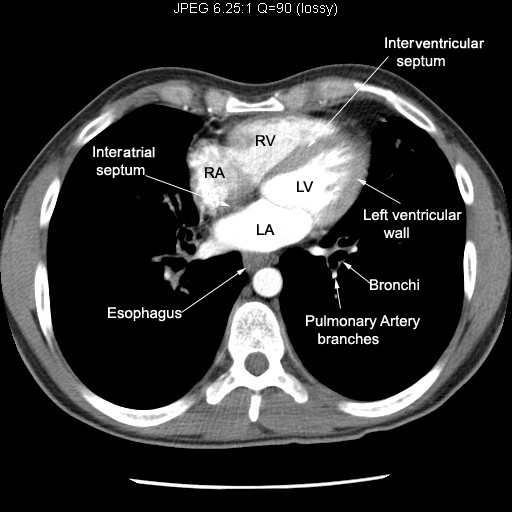

Thinking: Chest Pain

512 × 512